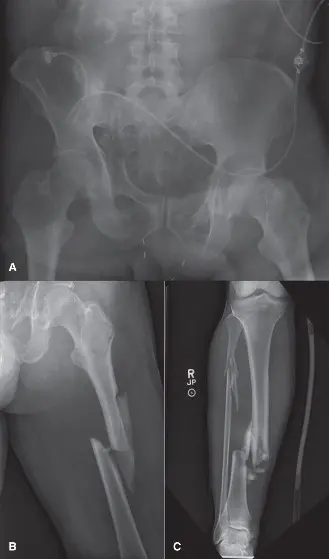

2. الفحوصات التصويرية السريعة

للحصول على صورة شاملة للإصابات، يتم إجراء فحوصات تصويرية سريعة:

*

الفحص الشامل (Pan-Scan CT):

غالبًا ما يتم إجراء فحص مقطعي محوسب (CT) شامل للرأس والعمود الفقري العنقي والصدر والبطن والحوض فورًا في قسم الطوارئ. هذا يوفر معلومات حيوية حول الإصابات الداخلية والكسور الرئيسية.

*

الأشعة السينية التقليدية:

يمكن إجراء أشعة سينية بسيطة للأطراف المشتبه في إصابتها لتقييم الكسور.

*

تصوير الأوعية الدموية (Angiography):

قد يكون ضروريًا في حالات الشك في إصابات الأوعية الدموية في الحوض أو الأطراف.

- التصوير: غالبًا ما يتم إجراء فحص شامل (CT للرأس، العمود الفقري العنقي، الصدر، البطن، الحوض) عند الوصول إلى قسم الطوارئ لتحديد الإصابات الأولية. الأشعة السينية البسيطة لإصابات الأطراف المشتبه بها عادة ما تكون كافية لتخطيط DCO. قد يكون تصوير الأوعية الدموية ضروريًا لإصابات الحوض أو الأوعية الدموية في الأطراف.